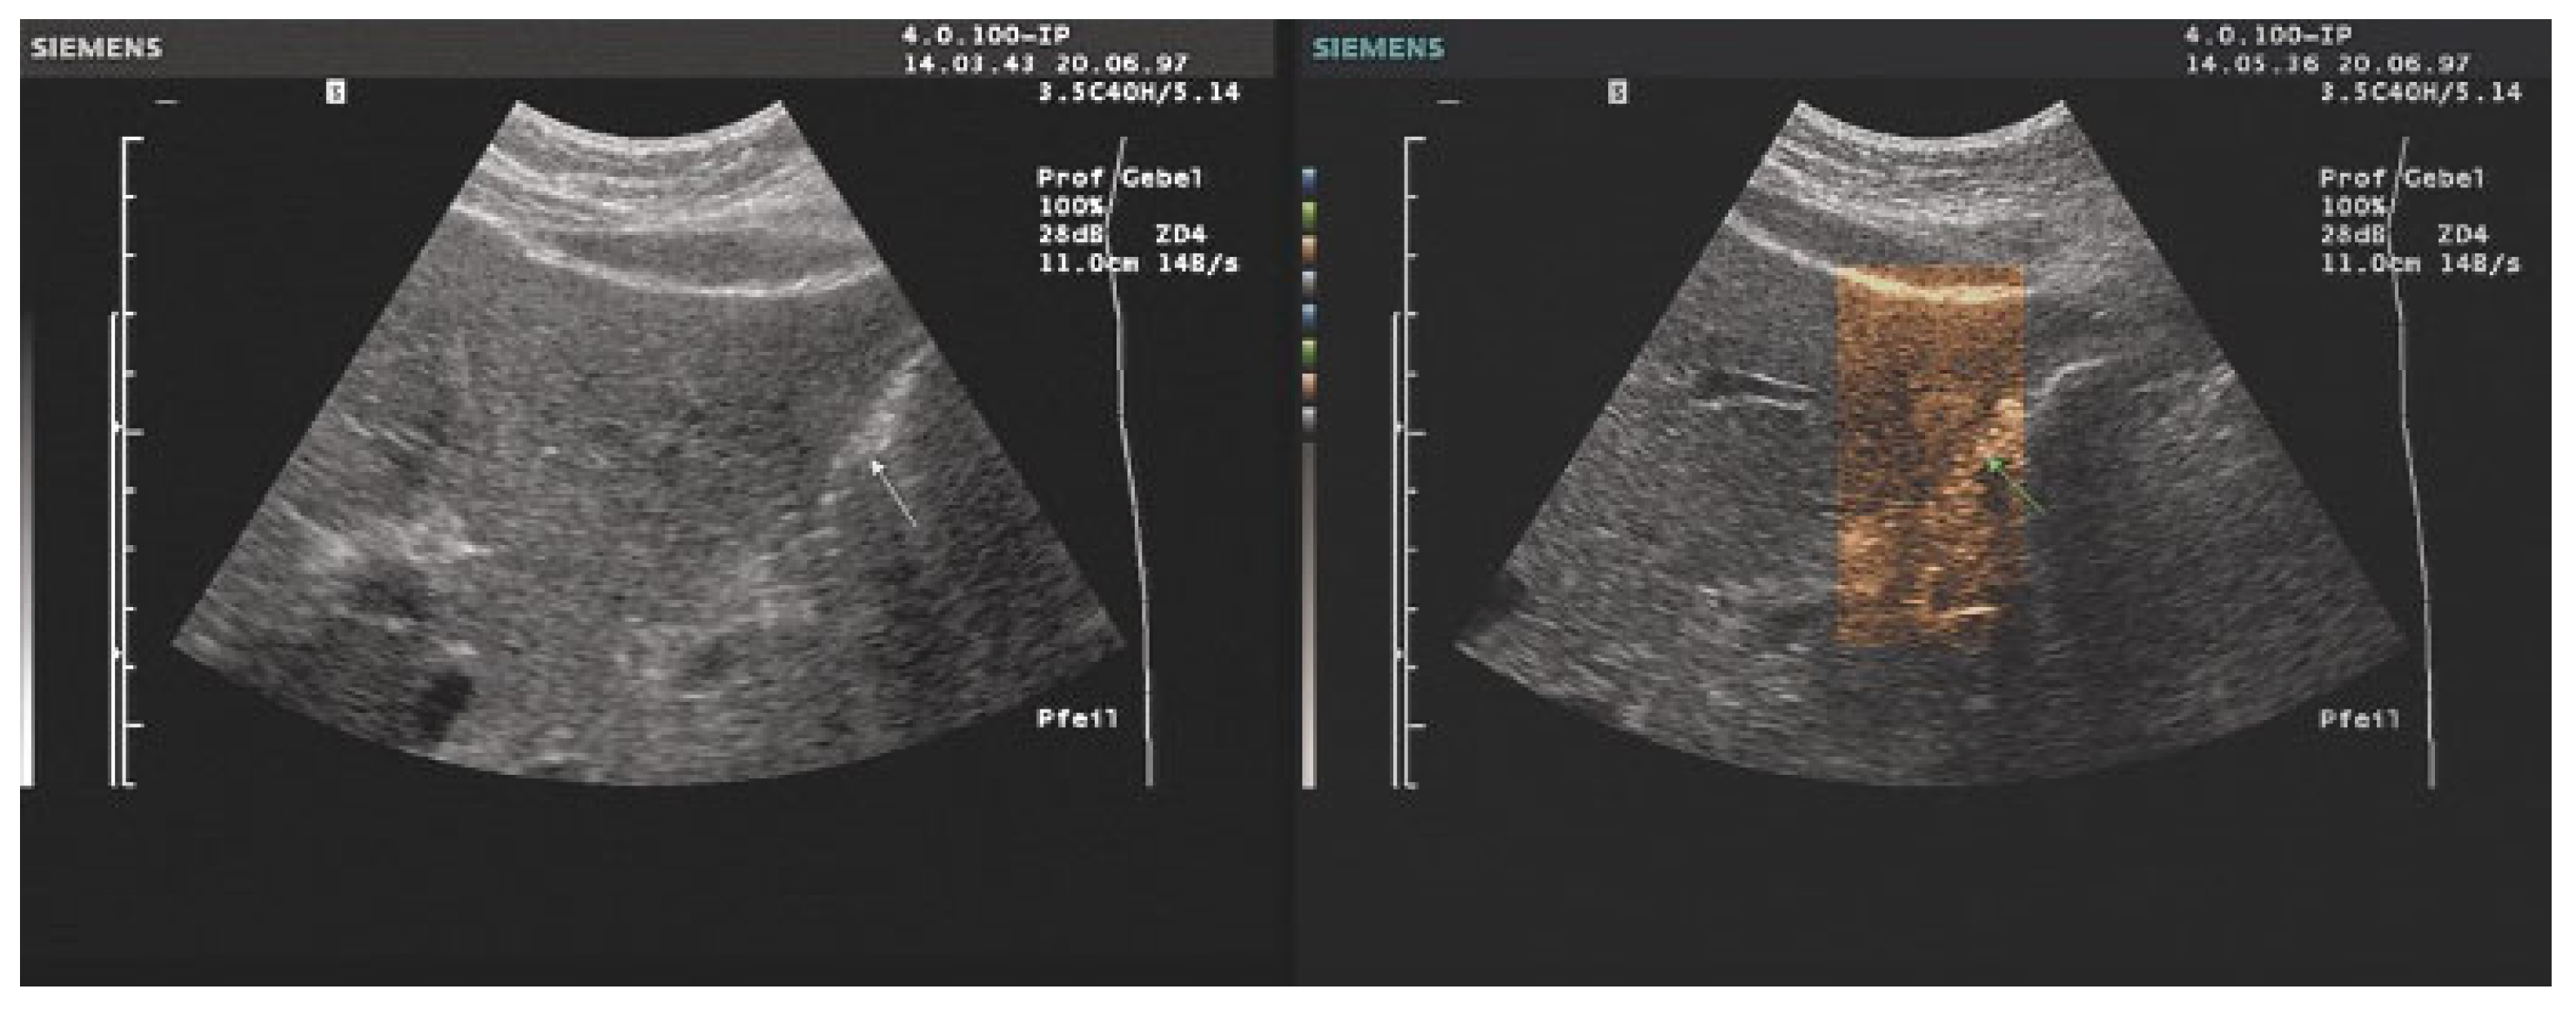

- The combination with speckle filters available in all high-end devices, similar to the low-pass filters used by Bleck et al. (1994) for tissue visualization [5], also yields significantly improved visualization results (Figure 5, Figure 6 and Figure 7). In principle, applications with new visualized texture analyses, such as random field models, are also conceivable [76,77].

- Bleck, J.S.; Gebel, M.; Witt, B.; Schmitt, K.J.; Breitkopf, P.; Westhoff-Bleck, M.; Wagner, S.; Göke, M.; Caselitz, M.; Schneider, A.; et al. Sonography under Daylight Conditions. Ultraschall Med. 1998, 19, 259–264. [Google Scholar] [CrossRef]

- Bleck, J.S.; Gebel, M.; Witt, B.; Schmitt, K.J.; Abel, J.; Westhoff-Bleck, M.; Thiesemann, C.; Wagner, S.; Göke, M.; Benter, T.; et al. Optimierung der Darstellung von Ultraschallbildern durch Einsatz histogrammgesteuerter, farbiger, artefaktfreier, tageslichtfähiger Look-Up-Tabellen. Ultraschall Klin Prax. 1995, 9, 204–207. [Google Scholar]

- Bleck, J.S.; Gebel, M.; Hebel, R.; Wagner, S.; Schmidt, K.; Kruip, S.; Westhoff-Bleck, M.; Wolf, M.; Thiesemann, C.; Manns, M. Tissue characterization using intelligent adaptive filter in the diagnosis of diffuse and focal liver disease. Ultrasound Med. Biol. 1994, 20, 521–528. [Google Scholar] [CrossRef]